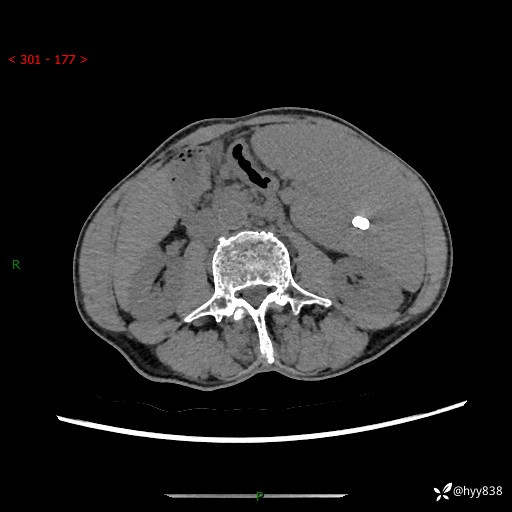

老年男性,脾大并脾脏弥漫粟粒状低密度,淋巴瘤 VS 肉芽肿 VS 血管瘤---结果公布

简要病史: 患者于3月前无明显诱因出现脾大,伴腹部轻微不适,具体不详,无腹痛、腹泻、腹胀,无头晕、头痛、乏力,无恶心、呕吐、呕血,无胸闷、气短、胸痛不适

上腹部CT平扫+增强